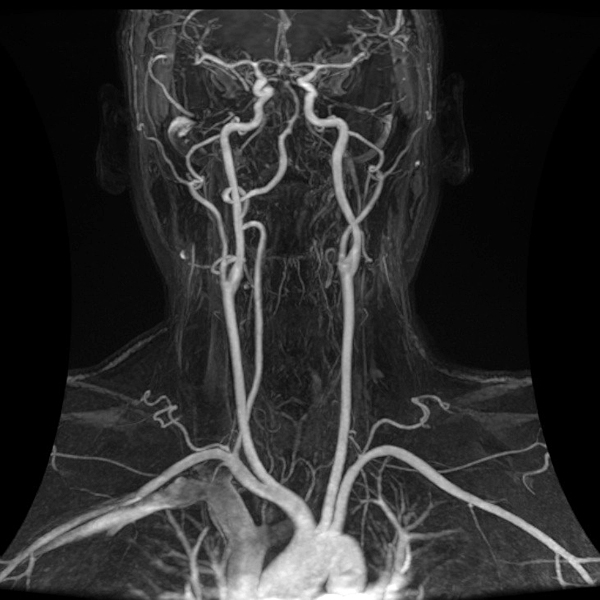

once i got back home and checked out my scans in osirix (the mac os x application to view DICOM medical imaging slides), i was blown away. talk about invasive: you haven't seen intimate until you've looked at photos of the inside of your body. the coolest part is since the scans were done in cross-sections, i can animate the scans so it looks like the beam is passing through my neck and head (all 800+ images). i've always known that inside my body was all sorts of muscles and veins and organs, but i guess i was hoping for something less messy, maybe circuit boards and memory chips instead. i know MRI's were first used in the late 60's, but this is my first time experiencing the technology in-person and it's pretty amazing. talk about futuristic! to be able to see with so much detail the insides of my body without having to cut me open! if scientists can do this, what else can they do? my only regret is they only imaged me from my shoulder up. i'd love to have a full-body scan. maybe i can fake some sort of internal injury and get my doctor to okay the procedure. i recommend anyone who's never had an MRI done to do so when they have the chance.